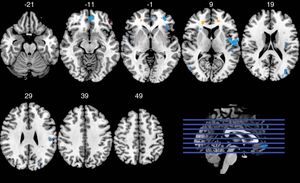

Gehirn-Scans: American Football verändert die Hirnstruktur (Foto: RSNA) |

Über MRTs wurden die Gehirne von 61 ehemaligen Spielern untersucht. Die MRT-Daten der drei restlichen Teilnehmer wurden aufgrund von zu viel Bewegung oder der Unmöglichkeit, die Untersuchung abzuschließen, ausgeschlossen. Das DTI-Verfahren wurde eingesetzt, um die strukturelle Integrität der weißen Gehirnmasse zu analysierten. Die MRT diente zur Beurteilung der Gehirnfunktion, während die Spieler eine Gedächtnisaufgabe zu lösen hatten.

Laut Mitautor Michael Clark ließen sich durch die Kombination beider Verfahren der Zusammenhang zwischen Struktur und Funktion erkennen, die beide durch einen Aufprall auf den Kopf beeinflusst wurden. Die Ergebnisse zeigten ein signifikantes Zusammenspiel von Karrieredauer und der Häufigkeit von Gehirnerschütterungen. Frühere College-Spieler mit drei oder mehr Gehirnerschütterungen verfügten im Vergleich mit jenen, die nur eine oder keine erlitten hatten, über eine geringere Integrität in einem größeren Bereich der weißen Masse. Das Gegenteil zeigte sich bei den Profispielern.

Spieler auf nicht auf Tempo ausgelegten Positionen mit vielen Gehirnerschütterungen verfügten in der frontalen weißen Substanz über eine verringerte Integrität und eine geringere Aktivierung bei den Gedächtnisaufgaben als jene mit einer Gehirnerschütterung oder weniger. Das war bei Geschwindigkeitsspielern nicht der Fall. Die beobachteten Wechselwirkungen zwischen erlittenen Gehirnerschütterungen und den Spielpositionen legt nahe, dass es wichtige Unterschiede bei den Verletzungsmechanismen gibt.

Die Heftigkeit, Position und Häufigkeit der Kopfverletzungen ist je nach Spielposition unterschiedlich. Offensive Backs erleiden Verletzungen bei einer größeren Geschwindigkeit. Linemen erleben mehr Schläge. Der Großteil passiert auf der Vorderseite des Helms. Dadurch könnte es zu lokalisierteren Schäden bei der frontalen weißen Substanz kommen als bei den Geschwindigkeitsspielern, bei denen die Verletzungen verteilter auftreten. Laut Guskiewicz wären daher Helme, die auf die Spielposition Rücksicht nehmen, gerechtfertigt.